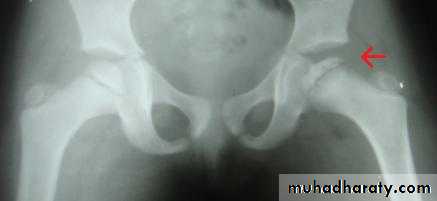

A group of conditions , in which no associated cause for a vascular necrosis can be found . But the osteochondritis are now regarded as being due to impaired blood supply associated with repeated trauma .A-Perth's disease :

A vascular necrosis of the femoral head in children , is the most important example of the osteochondritis . the plain radiograph changes :

1.the earliest change is increase in density and flattening of the femoral epiphyses which later on progress to collapse & fragmentation.

2.epiphysis widened & consequently the femoral neck enlarge and may contain small cyst .

3.joint space is widened but the accetabulum not affected .

4.with healing, the femoral head reforms but remain permanently flattened & therefore responsible for OA in later life .